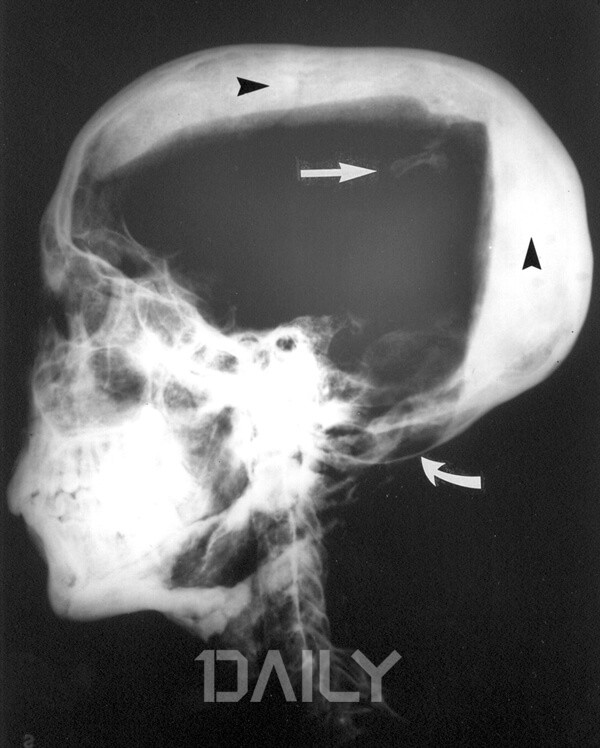

¿øÇÑ ¾ø´Â ÀúÁÖ´Â ¾ø±â¿¡, ÅõÅÁÄ«¸àÀÇ ÀúÁÖÀÎ ¡®ÆÄ¶ó¿ÀÀÇ ÀúÁÖ¡¯´Â ½Çü¸¦ ÇØºÎÇÒ Çʿ䰡 ÀÖ´Ù. ÅõÅÁÄ«¸à ¹«´ýÀÇ ¹ß±¼ ´ç½Ã ¹Ì¶óÀÇ X¼±À» ÃÔ¿µÇÑ °á°ú, ¸Ó¸®¿¡ µÐ±â¸¦ ¸ÂÀº µíÇÑ µÎ°³°ñ °ñÀýÀÌ ¹ß°ßµÇ¾î ÅõÅÁÄ«¸àÀÌ ¾Ï»ìÀ» ´çÇß´Ù´Â ¼³ÀÌ ¼³µæ·Â ÀÖ°Ô ÁÖÀåµÇ¾ú´Ù. ½ÇÁ¦ °í´ë ÀÌÁýÆ® ¿ª»ç¿¡ µû¸£¸é ÅõÅÁÄ«¸àÀÌ Á×Àº µÚ·Î Àǹ®Åõ¼ºÀÌÀÇ ¿ÕÀ§ °è½ÂÀÌ ÀϾ±âµµ Çß´Ù. À̸¦ ÅëÇØ ÀϺΠ°í°íÇÐÀÚµéÀº ÅõÅÁÄ«¸àÀÇ Á×À½À» ¡®¿ÕÀ§¸¦ ³ë¸° ÀÚ¿¡ ÀÇÇÑ »ìÀΡ¯À¸·Î Á¤ÀÇÇϰí ÀÖ´Ù.